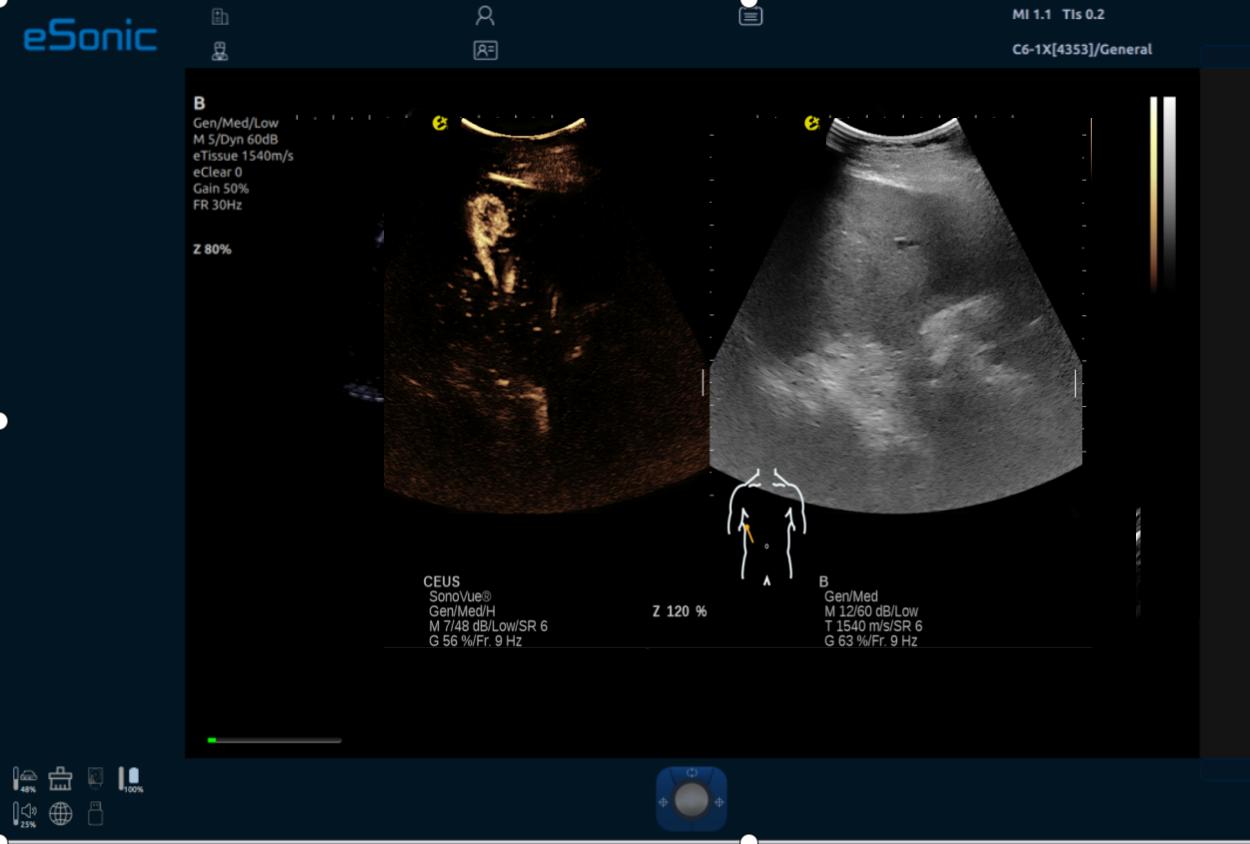

iPlane Contrast 超快速造影成像

AI Contrast 造影智能定量分析软件